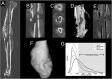

Thrombospondin-2 (TSP2) is a matricellular protein with increased expression during growth and regeneration. TSP2-null mice show accelerated dermal wound healing and enhanced bone formation. We hypothesized that bone regeneration would be enhanced in the absence of TSP2. Closed, semistabilized transverse fractures were created in the tibias of wildtype (WT) and TSP2-null mice. The fractures were examined 5, 10, and 20 days after fracture using microCT, histology, immunohistochemistry, quantitative RT-PCR, and torsional mechanical testing. Ten days after fracture, TSP2-null mice showed 30% more bone by microCT and 40% less cartilage by histology. Twenty days after fracture, TSP2-null mice showed reduced bone volume fraction and BMD. Mice were examined 5 days after fracture during the stage of neovascularization and mesenchymal cell influx to determine a cellular explanation for the phenotype. TSP2-null mice showed increased cell proliferation with no difference in apoptosis in the highly cellular fracture callus. Although mature bone and cartilage is minimal 5 days after fracture, TSP2-null mice had reduced expression of collagen IIa and Sox9 (chondrocyte differentiation markers) but increased expression of osteocalcin and osterix (osteoblast differentiation markers). Importantly, TSP2-null mice had a 2-fold increase in vessel density that corresponded with a reduction in vascular endothelial growth factor (VEGF) and Glut-1 (markers of hypoxia inducible factor [HIF]-regulated transcription). Finally, by expressing TSP2 using adenovirus starting 3 days after fracture, chondrogenesis was restored in TSP2-null mice. We hypothesize that TSP2 expressed by cells in the fracture mesenchyme regulates callus vascularization. The increase in vascularity increases tissue oxemia and decreases HIF; thus, undifferentiated cells in the callus develop into osteoblasts rather than chondrocytes. This leads to an alternative strategy for achieving fracture healing with reduced endochondral ossification and enhanced appositional bone formation. Controlling the ratio of cartilage to bone during fracture healing has important implications for expediting healing or promoting regeneration in nonunions.